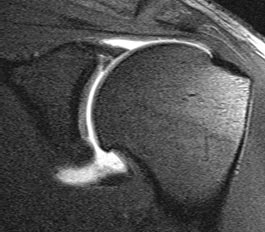

Lesões do Tendão do Supraespinhal.

Lesão Supraespinhal

Tendão Reparado Após Artroscopia de Ombro